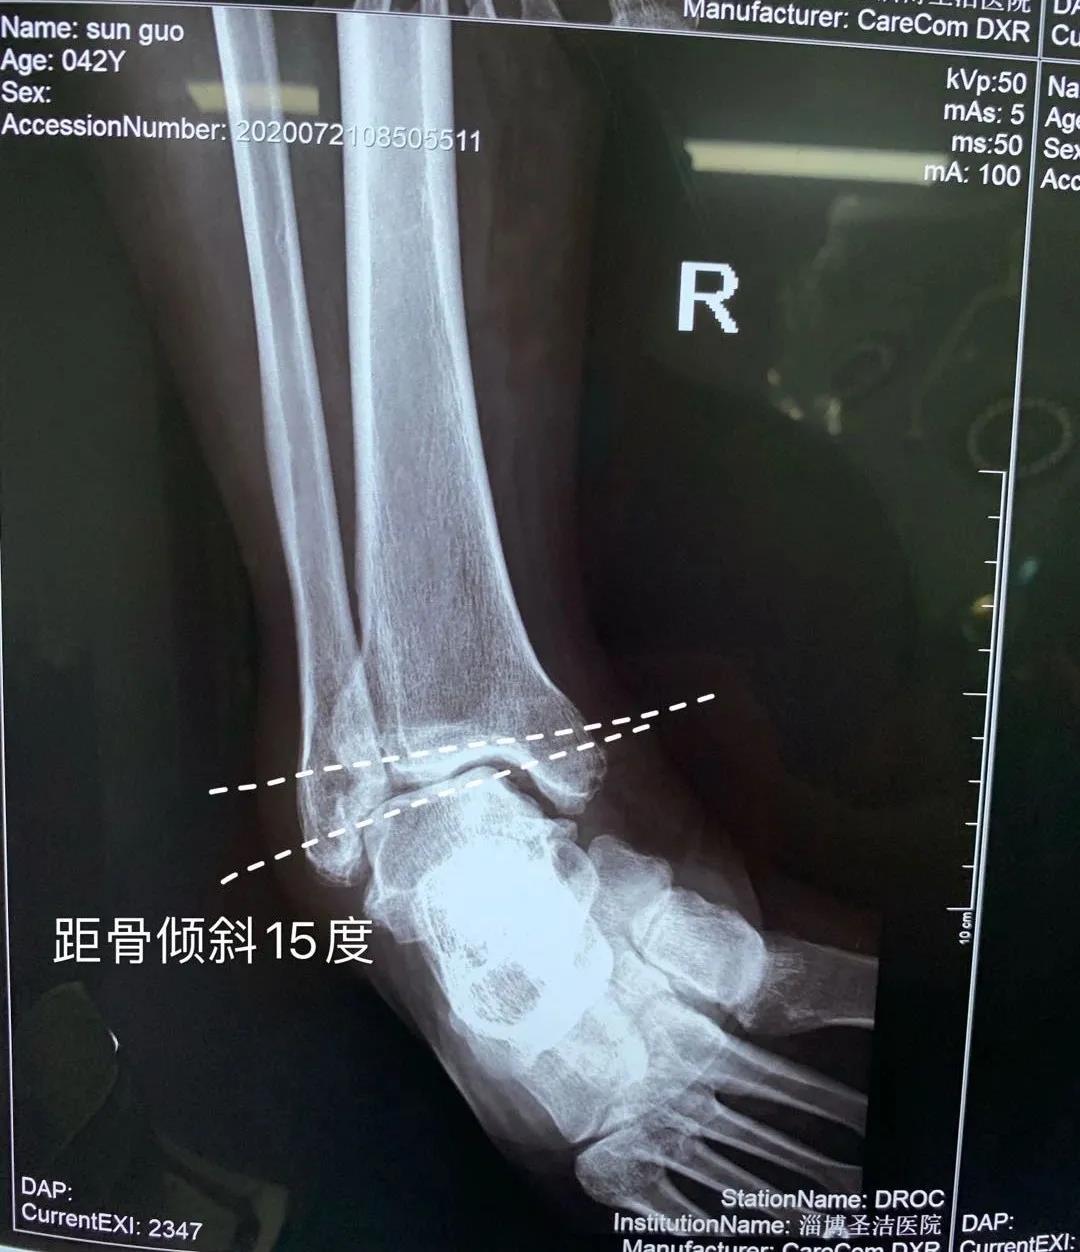

近日,醫(yī)院骨二科成功治療一位踝關(guān)節(jié)反復(fù)疼痛病人。患者李某,男,42歲,踝關(guān)節(jié)外傷導(dǎo)致外側(cè)韌帶損傷踝關(guān)節(jié)不穩(wěn),長(zhǎng)期沒(méi)有及時(shí)治療導(dǎo)致踝關(guān)節(jié)骨關(guān)節(jié)炎的發(fā)生。患者踝關(guān)節(jié)疼痛不能長(zhǎng)距離行走這是術(shù)前應(yīng)力位片提示踝關(guān)節(jié)距骨傾斜,踝關(guān)節(jié)踝前撞擊綜合癥,給予踝關(guān)節(jié)鏡下關(guān)節(jié)腔清理,骨贅切除,并給予外側(cè)韌帶重建恢復(fù)關(guān)節(jié)穩(wěn)定性。目前,患者手術(shù)后的踝關(guān)節(jié)穩(wěn)定,功能恢復(fù)良好,即將康復(fù)出院。